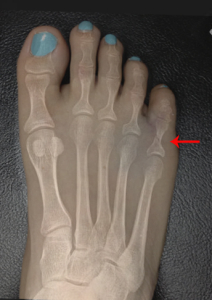

hawkins sign

霍金斯標識.是在距骨圓頂指示存活力6至8週的距骨骨折後的軟骨下透亮頻帶。它是在前後視圖中可見的,但很少出現在側位片。

如果全部或部分呈現陽性霍金斯符號被檢測到,這是不可能在損傷後的稍後階段發展成缺血性壞死.是一種很好判斷方法.